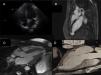

Multimodality imaging of the left ventricular apical aneurysm. (A) Echocardiogram, 4-chamber view, showing no remarkable changes; (B) cardiac magnetic resonance imaging with late gadolinium enhancement depicting myocardial delayed enhancement restricted to the wall of the left ventricular apical aneurysm; (C) cardiac magnetic resonance imaging at end-systole demonstrating the lack of systolic thickening of the left ventricular apical aneurysm wall; (D) computed tomography image of the left ventricle clearly showing the thinning of the left ventricular aneurysm wall compared to the surrounding myocardium.

On the day that he presented to our department an electrocardiogram (ECG) was performed (Figure 1), which revealed monomorphic ventricular tachycardia with right bundle branch block morphology and superior axis, with a ventricular rate of 256 bpm. As the patient was stable, amiodarone infusion was started, achieving sinus rhythm. His ECG in sinus rhythm showed no changes (Figure 2). The echocardiogram (Figure 3A) revealed no structural abnormalities and the physical examination and laboratory tests showed no remarkable findings.

In order to exclude structural cardiac abnormalities it was decided to perform cardiac magnetic resonance imaging (Figure 3B and C) that exhibited a left ventricular apical aneurysm: “a saccular apical formation with a thin wall on late gadolinium enhancement, without any scarring of the surrounding myocardium”. He underwent computed tomography coronary angiography that excluded coronary disease and described the same left ventricular apical formation (Figure 3D).